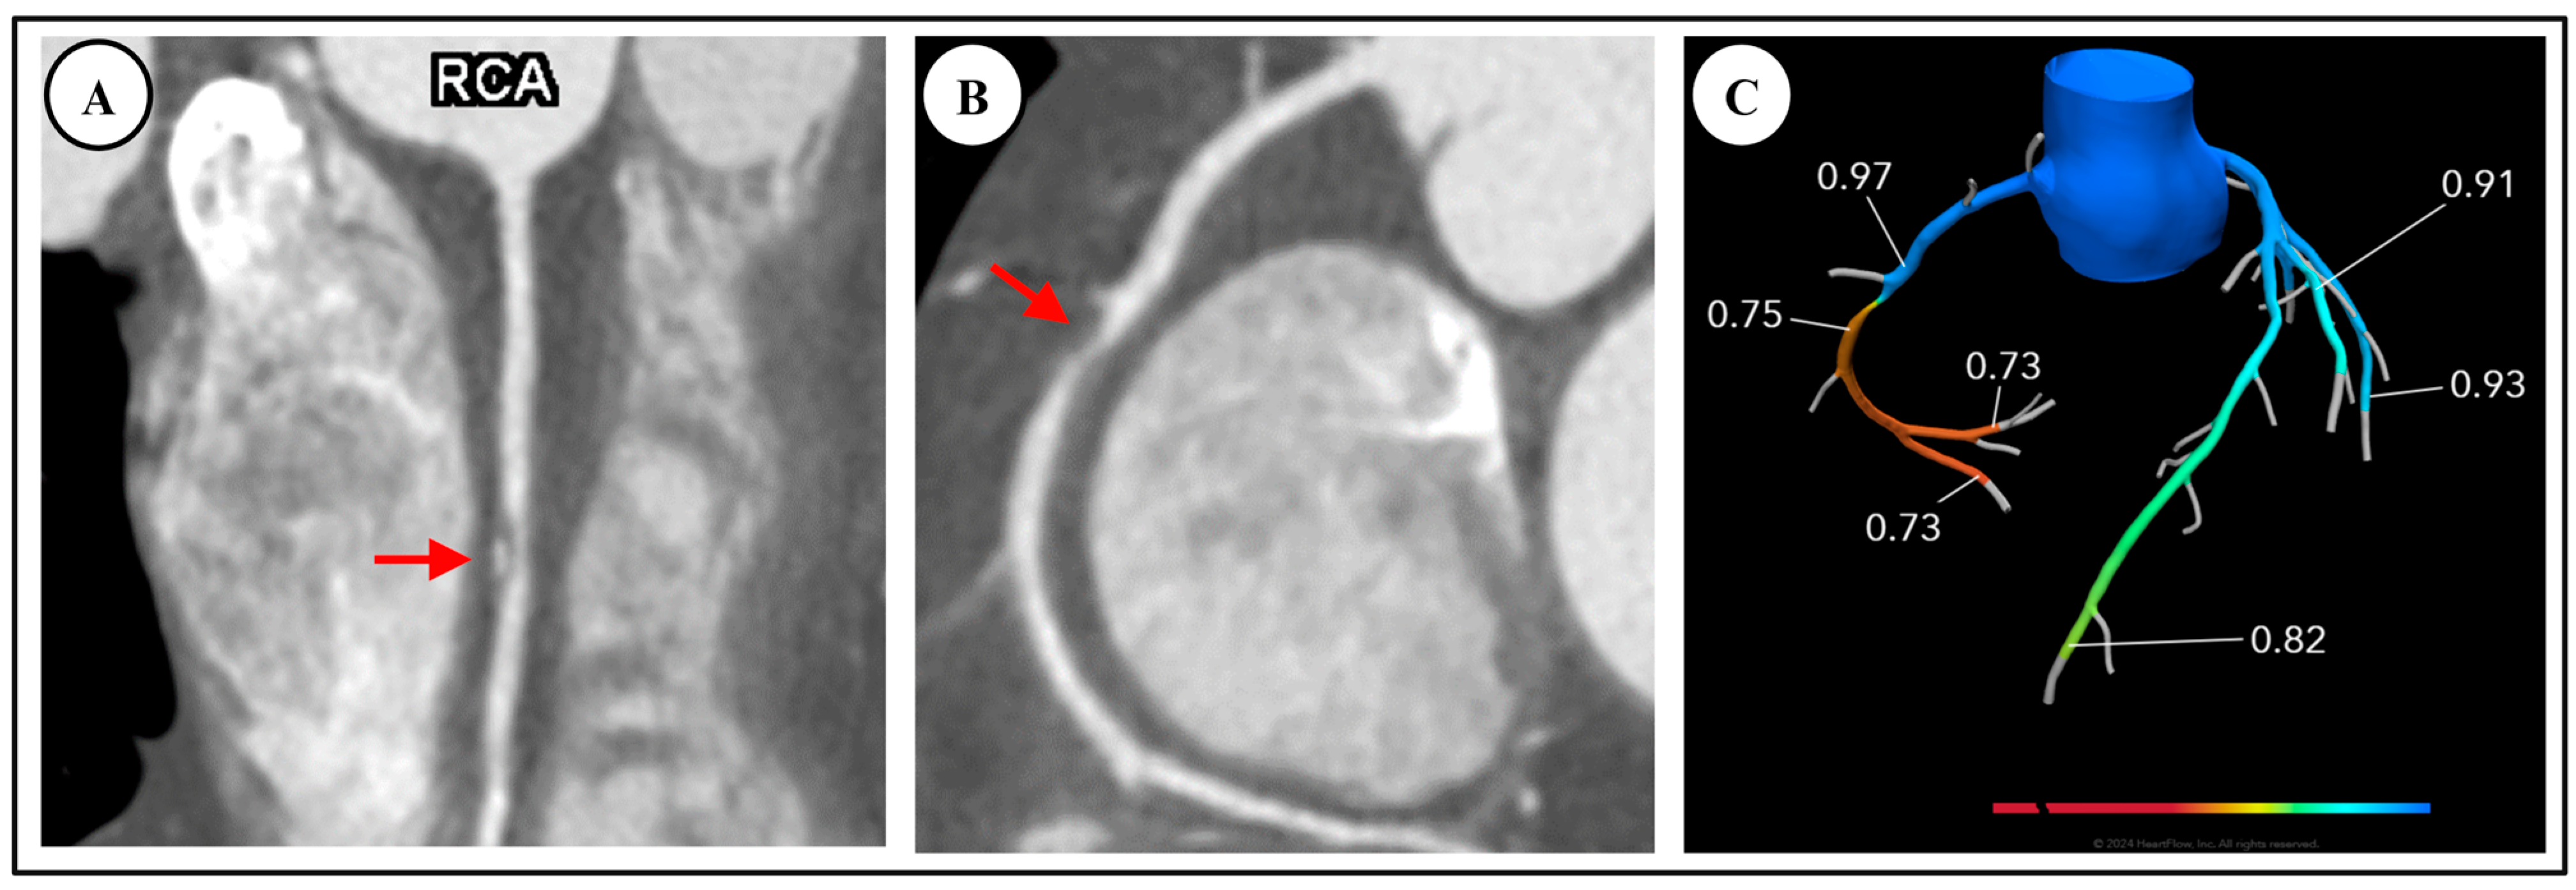

4.1. Fractional Flow Reserve—Computed Tomography (FFR-CT)